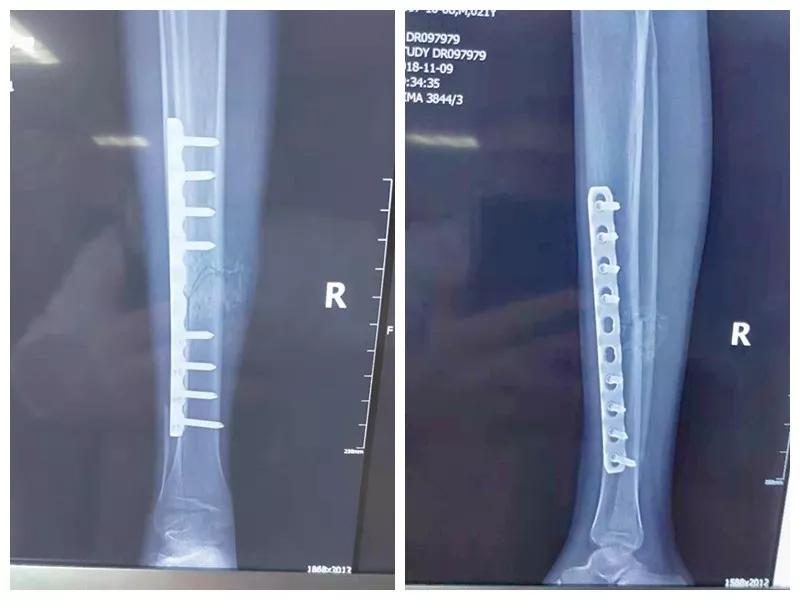

这名21岁的男性患者一个月前因车祸致伤,在当地某三甲医院确诊为右胫腓骨粉碎性骨折,骨折移位明显,建议手术治疗,因既往患严重慢性再生障碍性贫血病史16年,一般状况差,需长期输注血液制品维持三系细胞水平,麻醉及手术风险极高。虽经当地积极内科治疗,患者一般状况仍差,无法耐受手术治疗。患者及家属经多方打听,抱着最后一丝希望来到六合彩生肖 骨二科求治。

骨二科张延平主任接诊后经仔细询问病史,详细阅读近期X线、CT等病历资料,认为患者骨折移位明显,目前骨折无任何愈合迹象,若保守治疗,骨折将无法愈合,后期不能下地活动,严重影响患者生活质量。同时患者合并慢性再障,血常规结果各项指标均极低,围术期发生麻醉意外、大出血、感染等风险极高;而六合彩生肖 作为西安市级最大的三甲综合医院,综合实力深厚,既往相关疾病治疗经验丰富,多次通过多学科诊治为合并复杂内科疾病患者保驾护航,为患者创造手术时机,提高患者生活质量,遂将患者收住院。住院后,立即成立了由张延平主任、杨寅副主任、山卉护士长、梁晨主治医师、刘邦定主治医师、李鑫护师组成的手术治疗小组。经初步检查,患者血常规结果较当地检验结果更差,三系细胞均极低,其中血小板仅为1(正常值为100-300),血红蛋白55g/L。遂立即请血研所李罡灿主任医师会诊,给予升高白细胞、纠正贫血、升高血小板等治疗,经积极治疗患者血常规各项指标均较入院时改善。张延平主任再次组织由血研所李罡灿主任医师、麻醉科崔晓岗主任、感染科付建军主任、药剂科韩小年副主任药师等参加的术前讨论。讨论后一致认为患者目前各项指标虽然较入院时改善,但因其慢性再障病史长,骨髓造血及储备能力极差,围术期发生大出血、伤口感染甚至全身感染等风险仍极高,术中及术后需准备大量血小板防止大出血,同时需高度警惕手术切口、取骨区术后发生感染。为尽快为患者施行手术,治疗小组积极联系输血科为患者备血,并为患者制定了围术期抗感染方案;在六合彩生肖 输血科存血量严重不足的状态时,输血科张养民主任亲自联系市中心血站为患者准备手术中及术后所需的血小板制品。手术小组为患者制定了周密的手术方案及风险预案,10月31日,在麻醉科王永宏副主任医师、手术室高洁、赵耀护师的配合下,为患者施行了右胫骨粉碎性骨折切开复位、髂骨取骨植骨内固定术,手术历时70分钟,安全返回病房。术后患者渗血多,1周内连续每日平均渗血超过100ml,并出现发烧,最高39℃,复查血常规三系细胞较术前再次明显降低。李罡灿主任医师、付建军主任、韩小年副主任药师多次来科会诊,及时调整患者的治疗方案,输血科再次为患者的救治提供了强有力的支援和保障。在山卉护士长带领的护理团队精心护理下,患者未发生压疮等卧床并发症。目前该患者术后恢复良好,已出院进行下一步康复治疗。